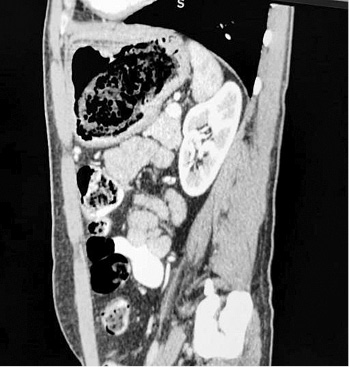

A thirty two years old male patient presented to our surgery department with complain of postprandial abdominal pain, early satiety and occasional vomiting episodes. He lost 5–6 kg in the past 6 months. The symptoms were present for the last 1 year. No comorbidity was reported. Previously he underwent a gastroscopy in another hospital where a stomach bezoar and large ulcer was diagnosed (Figure 1). Plain x-ray (Figure 2), computerized tomography (CT) scan (Figures 3 and 4) and gastroscopy were conducted in our institution. The gastroscopic examination reported giant rough bezoar impossible for endoscopic retrieval.

Figure 4. Sagittal computerized tomography scan